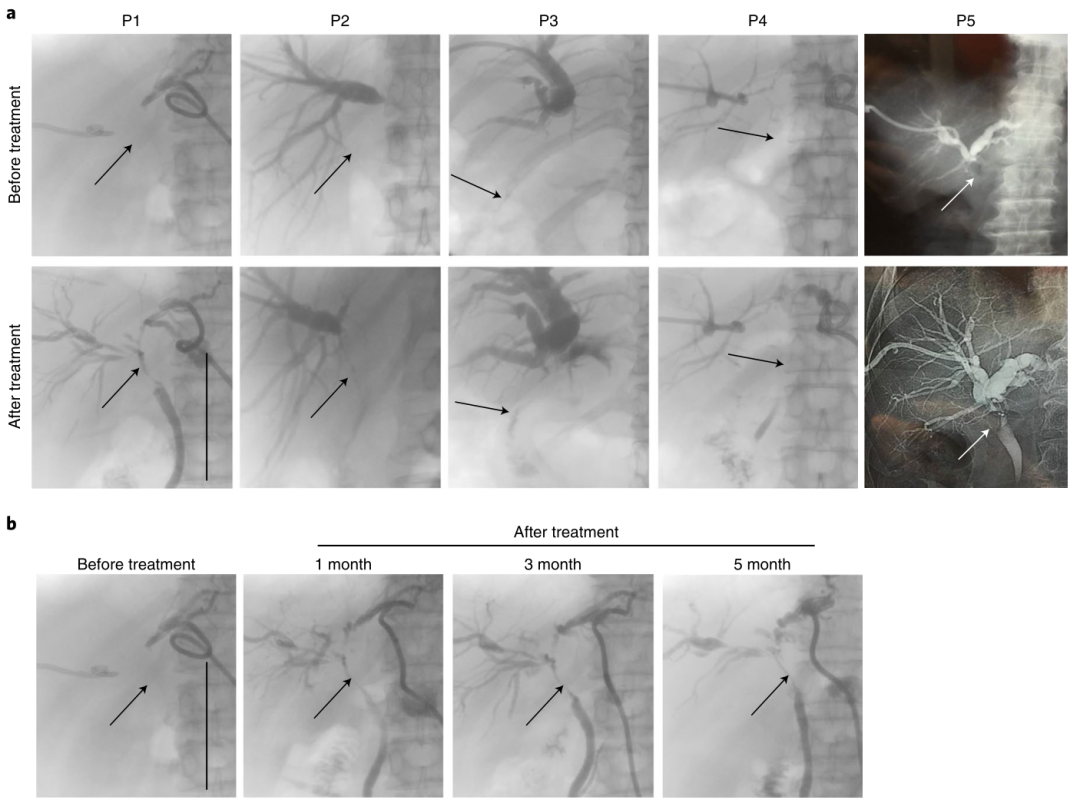

使用MTX-TMP有效治疗阻塞性CCA